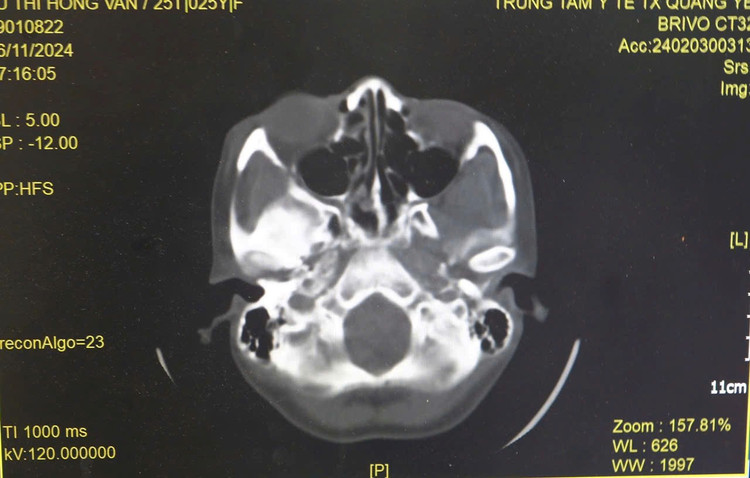

| Hình ảnh tổn thương trên phim chụp - ảnh BVCC |

Kết quả khám và cận lâm sàng cho thấy, khuôn mặt chị V. bị sưng nề, biến dạng một bên, vùng mắt phải sưng và bầm tím, vỡ thành trước hốc mắt phải, xét nghiệm bạch cầu tăng, ổ răng có giả mạc, há miệng hạn chế.